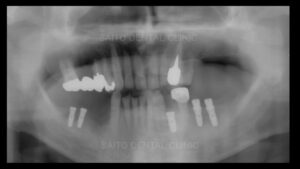

そして奥歯にインプラント治療をしていきますが右下の部分は顎の骨の中の神経付近まで

歯周病によって顎の骨が溶けてしまっているためインプラントができません

また、骨を作る手術も神経が近いため麻痺の可能性を考えるとそれもできません

そこで右下は手前の歯をインプラントで引っ張って周囲の骨ごと引っ張ってその手前に

インプラントを植える治療方法としました

矯正治療後インプラントに被せ物をし、上の顎は予算を相談し部分義歯を装着しました

治療前と治療後の状態です ご本人の希望で保険治療でできると所はなるべく保険治療で

治療をし、どうしてもここはしっかり治しておいた方がいいところに治療費用をかけることによって

末長くしっかり噛める状態を作ることができました